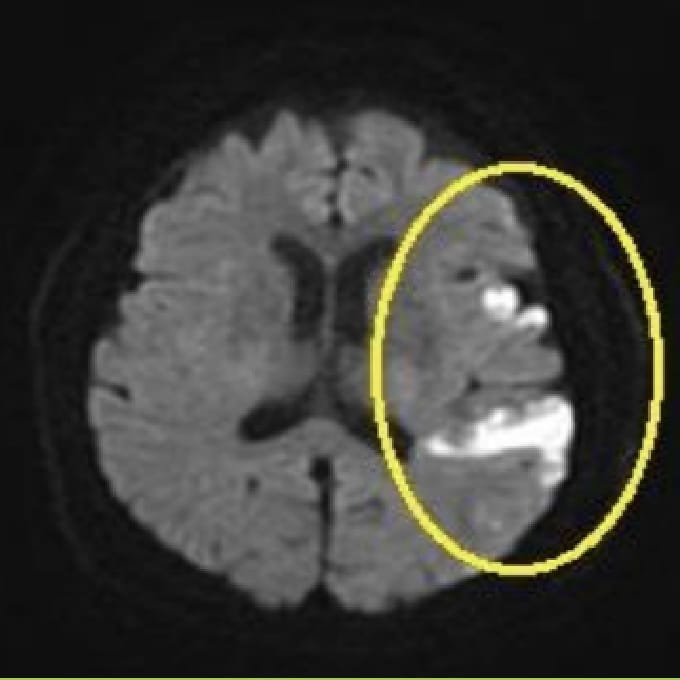

脳梗塞

MRIは、脳の断面画像を撮影し、脳そのものの状態を確認する検査です。X線を使用せず、脳梗塞の痕跡(無症候性を含む)や出血の跡、腫瘍などの異常がないかを調べます。MRAはMRIの撮影法の一つで、脳や頸部の血管を画像として写し出し、血管の形や流れの状態を確認する検査です。未破裂脳動脈瘤の疑い、血管の狭窄・閉塞など、脳卒中リスクにつながる所見の確認に役立ちます。